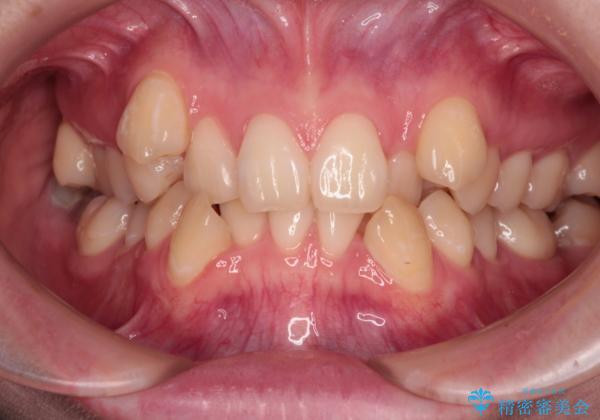

上下の八重歯とクロスバイト ワイヤー装置での抜歯矯正

- 八重歯とクロスバイトを気にして来院された患者様です。

上下ともに八重歯が顕著であり、前歯のクロスバイトがあったため、上下左右の第一小臼歯4本を抜歯し、ワイヤー装置での抜歯矯正を行うこととしました。

20歳ということもあり、歯の移動速度が非常に速く、1年強という短期間であっという間に治療を終えることができました。